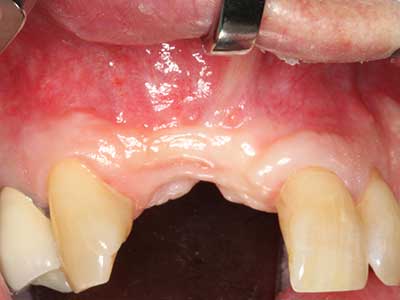

Abb. 2: Vertikaler und horizontaler seitlicher Oberkieferdefekt bei hoher Lachlinie mit Indikation zur präimplantologischen Rekonstruktion.

Abb. 12: Nach sechs Monaten Heilungsperiode zeigt sich ein in allen Richtungen ausreichend dimensionierter, vitaler Kieferkamm.